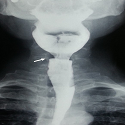

Cricopharyngeal bar

Suresh Chander Sharma, Pirabu Sakthivel

PAMJ. 2017; 27: 288. Published 23 August 2017